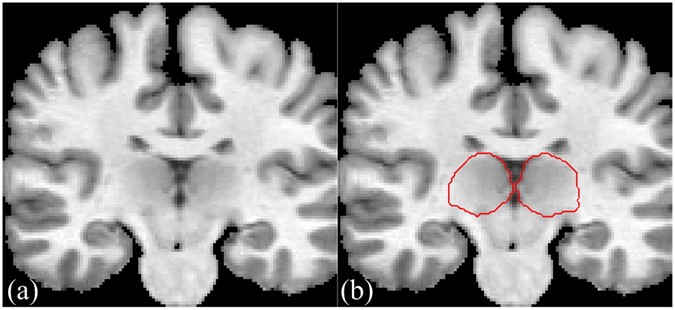

The thalamus plays a critical role in human brain function. It is the largest, most internal structure of the diencephalon. Segmentation and characterization of the thalamus from brain magnetic resonance images (MRI) are expected to help noninvasive diagnosis and treatment. Thalamus segmentation has become more and more important for a wide range of clinical and research applications. For example, the thalamus changes in terms of volume and intensity are involved in a large number of diseases, such as Parkinson’s disease, multiple sclerosis and schizophrenia. Expert manual segmentation of thalamus from MRI data is still the gold standard, but it is labor intensive, and the segmentation results are not reproducible. The thalamus has no clearly contrasted boundaries in MR T1-weighted images, this issue is illustrated by Fig. 1, where no obvious thalamus boundary can be observed. It is a difficult challenge even for an expert radiologist.

MR T1-weighted image (a) an image slice obtained from a 3-D thalamus MR image. (b) The manually-delineated thalamus boundary shown by the red contour, superimposed on the original image in (a).